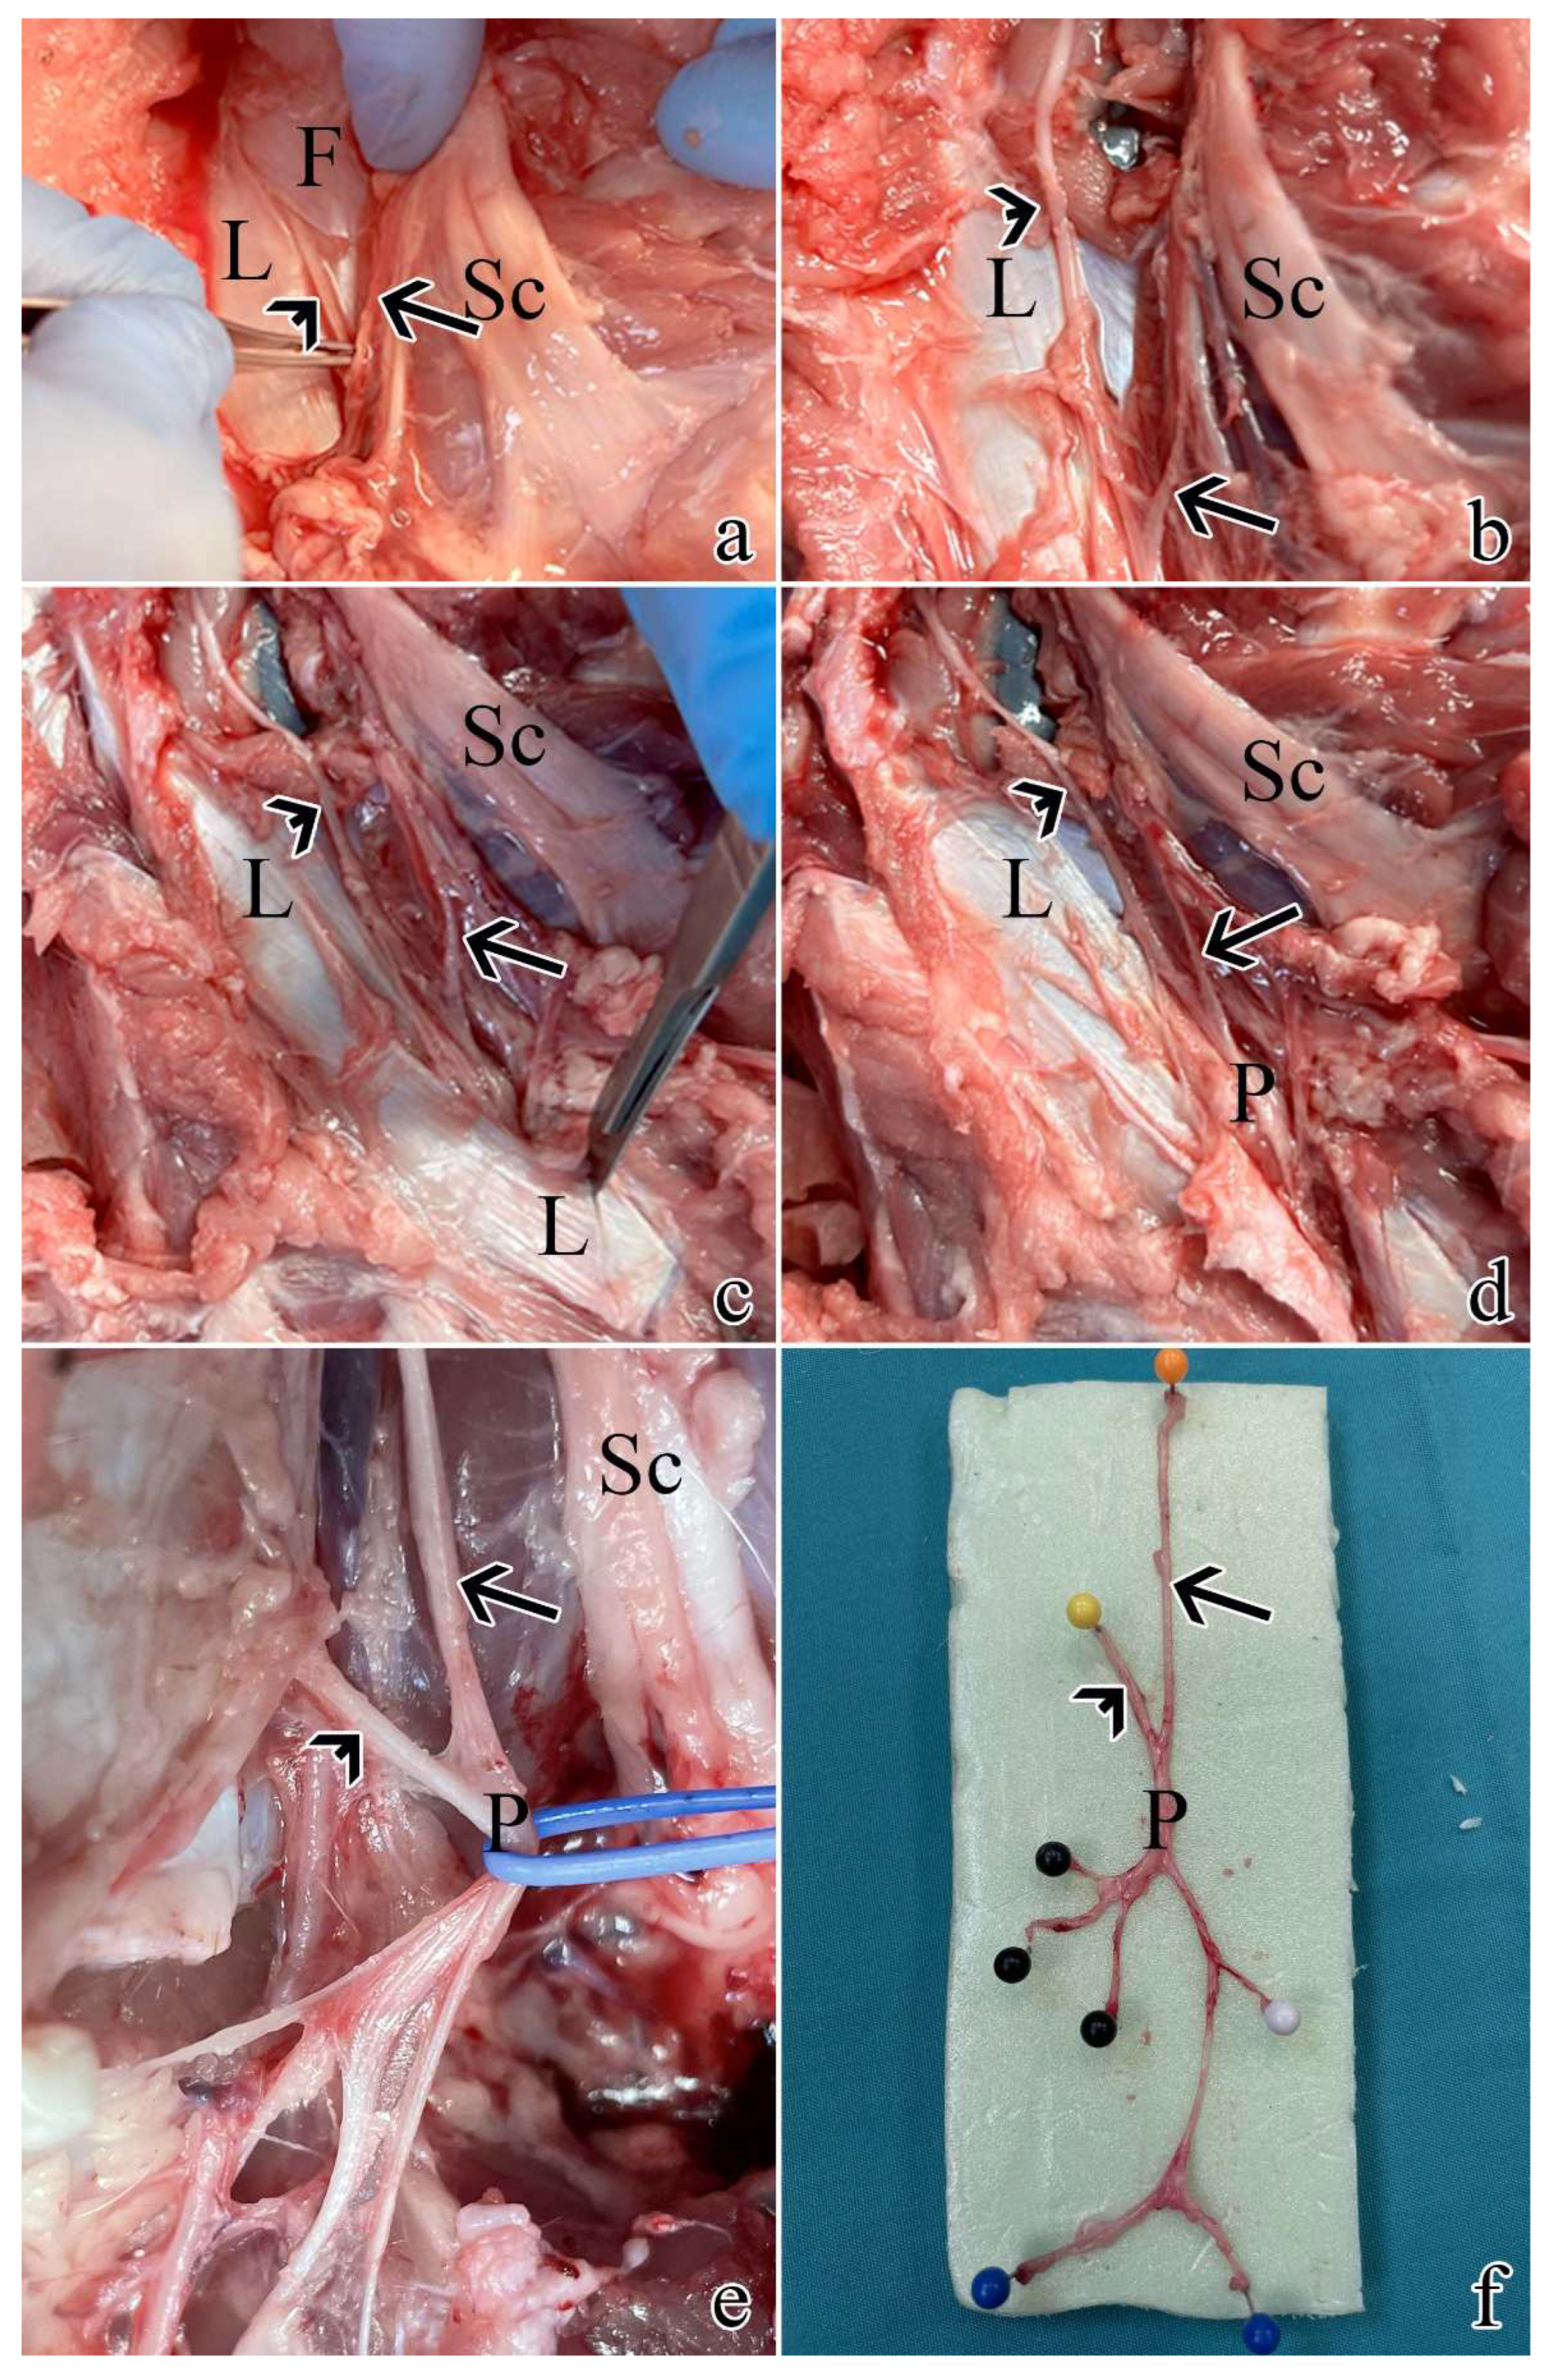

Post-sacrifice dissection allowed the sampling of all pudendal nerve origins and branches: the swine pudendal nerve consisted of two sacral origins, a common segment, and two main branching segments (a cutaneous and a splanchnic one):

The rostral sacral origin was identified as departing from S1 and lies between the sciatic nerve and the pudendal vein and artery.

The caudal sacral origin was identified as departing from S2 and is mostly covered by the thoracolumbar fascia.

The common segment goes caudally and is covered by the sacrospinous ligament.

The cutaneous branch gives rise to 2-3 individual nerves.

The splanchnic branch also originates 2-3 individual nerves.

These mentioned findings are summarized in Figure 1.

Figure 1. Post-sacrifice dissection of all pudendal nerve origins and branches: a) exposure of S1 as described in Section 4.1. using a muscle and ligament-sparing transgluteal surgery; b) the thoracolumbar fascia was removed rostrally and caudally to expose S2; c) caudal dissection allowed the identification of the sacrospinous ligament; d) resection of the ligament allowed to visualize the proper pudendal nerve; e) the pudendal nerve gives rise of multiple branches; f) pudendal nerve sample with its S1 and S2 origins and branches: black pins highlight the splanchnic component, while blue and white pins the cutaneous ones. Arrows highlight S1, while arrowheads indicate S2. L = sacrospinous ligament; F = thoracolumbar fascia; Sc = sciatic nerve; P = pudendal nerve.